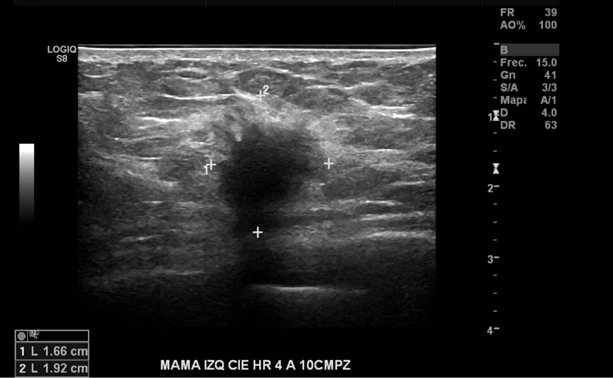

Nódulo sólido, de bordes irregulares, con sombra acústica posterior, gran tamaño, no palpable en CIE HR 4 a 10 cm pz en mama izquierda. Por su ubicación, no es visible en Mx

En el cuadrante inferior externo de la mama izquierda a la hora 4 a 10 cmp, se observa un nódulo hipoecogénico, ovalado, de bordes irregulares con microcalcificaciones en su interior, escasamente vascularizado y bien definido, de 20 mm de diámetro.

Nódulo mamario izquierdo altamente sugerente de malignidad.

BIRADS US 5

Se sugiere correlación histológica.